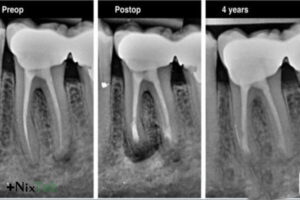

در واقع آبسههای تکرارشونده حتی پس از عصبکشی موفق، مهمترین نشانه شکستگی ریشه هستند. در چنین شرایطی، دندانپزشک دندان را میکشد تا از آسیب بیشتر جلوگیری کند.